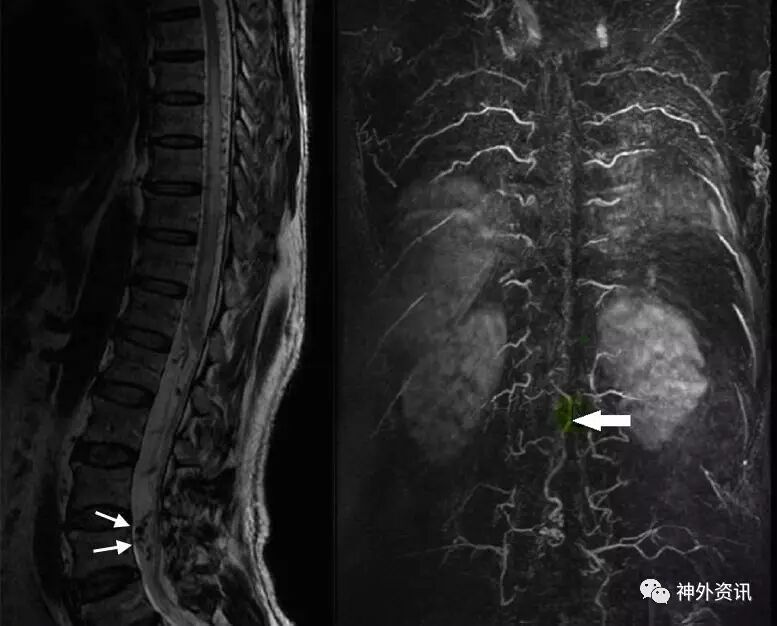

入院后进一步行CTA检查提示椎管内扩张的血管起始于左侧腰4椎间孔,左侧腰动脉的分支从腰5椎间孔进入椎管(图2)。

图2. CTA检查提示椎管内扩张的血管起始于左侧腰4椎间孔,左侧腰动脉的分支从腰5椎间孔进入椎管。左侧腰4/5椎板间隙可见椎管内的扩张血管。